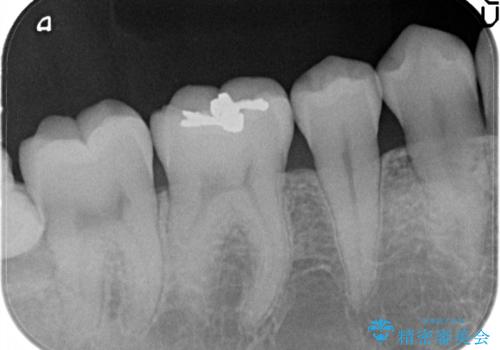

メタルフリーの治療 セラミックインレー

- メタルインレーによる審美障害を主訴に来院されました。

セラミックインレーに治療を行っております。

e-max プレスインレーにて修復治療を行っているため適合性及び審美性の高い治療を行うことができます